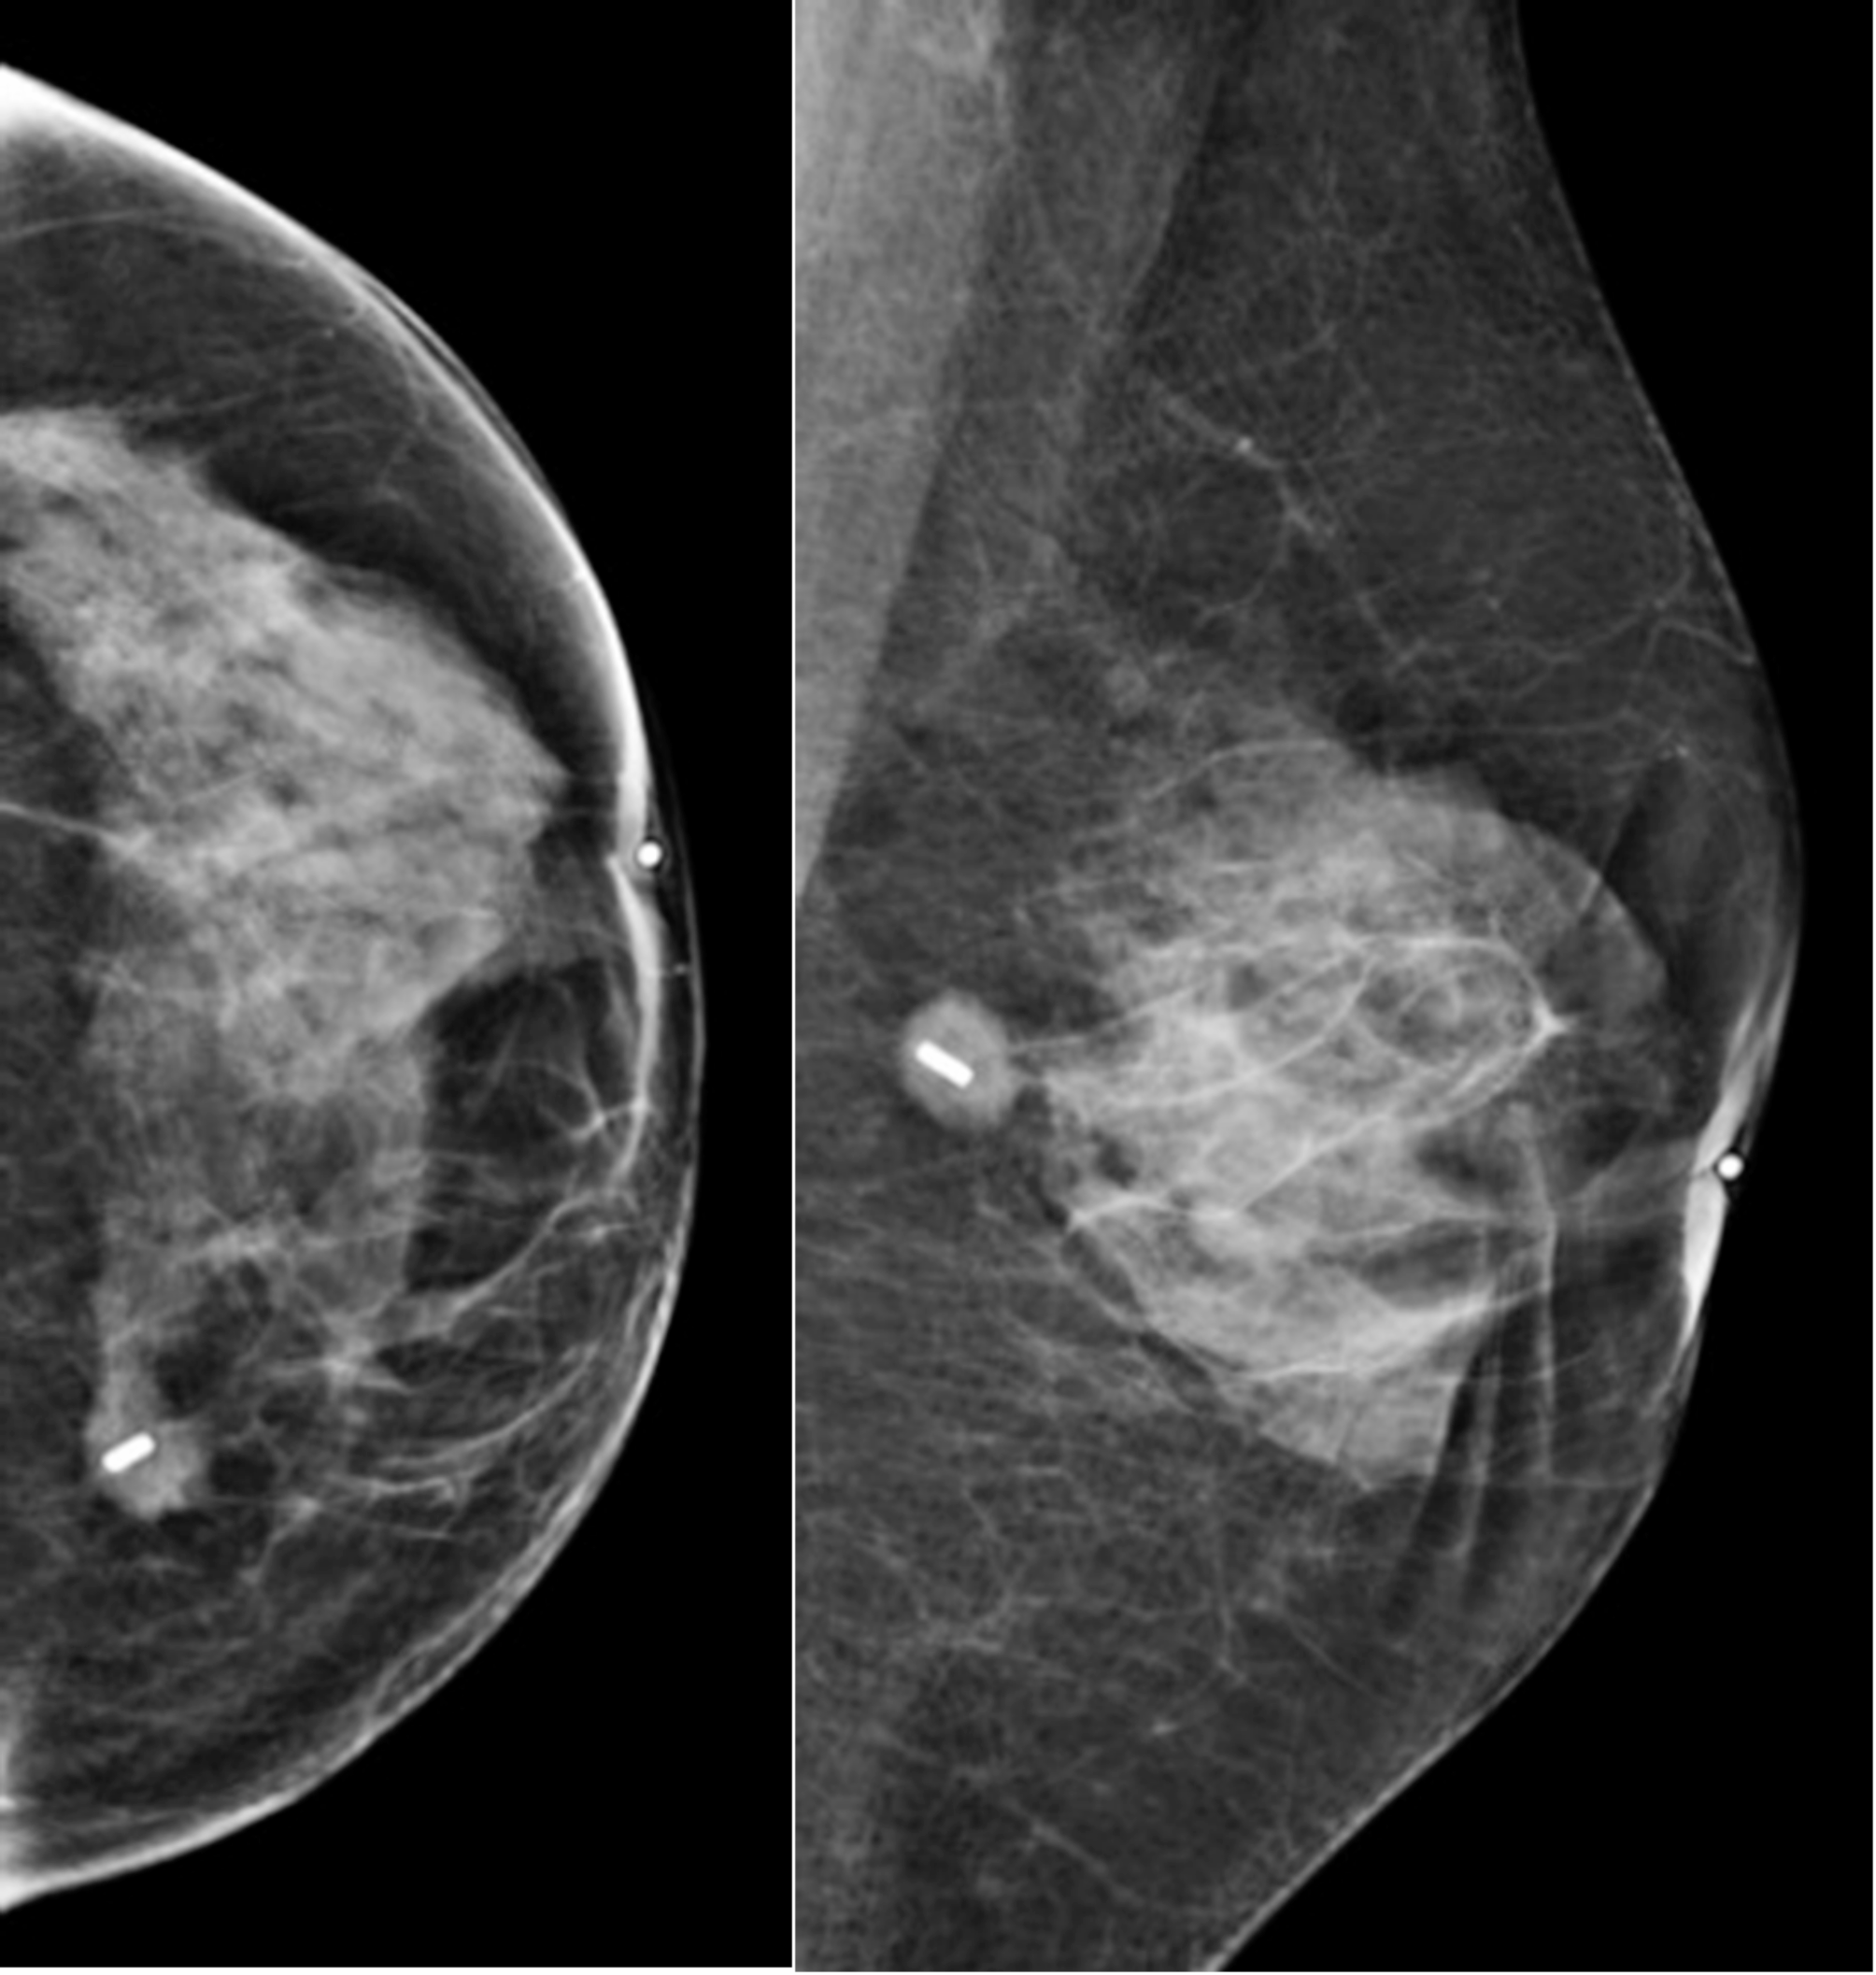

Fig. 1

Pre-operative mammographic control of the magnetic marker. Sub clinical centimetric tumor at the union of the inner quadrants of the left breast, corresponding to a ductal invasive carcinoma, luminal A, without adenopathy.